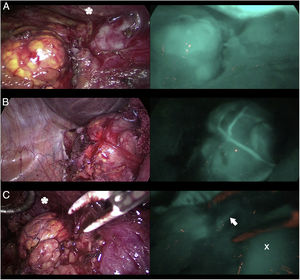

DiscussionThe use of ICG in endocrine surgery is a safe and effective technique. The recommended dose is 5mg, both in adrenal and thyroid surgery, although its administration can be repeated on several occasions, if necessary. In the field of adrenal surgery (Fig. 1), ICG shows clear adrenal hyperfluorescence in the first minute, maximum after 5min and visible up to 20min after infusion, which allows it to be perfectly differentiated from the surrounding fatty tissue and ensure its dissection and complete resection. In addition, the visualization of adrenal vascularization with ICG, although inconstant, can provide greater control during dissection maneuvers and thus reduce the rates of hemorrhagic complications, as well as those derived from glandular manipulation. It is worth mentioning that tumors of the adrenal cortex appear to be hyperfluorescent, while spinal tumors and malignant tumors would be hypofluorescent compared to the rest of the gland, which is of special interest in partial resections. Similarly, the use of ICG in cervical endocrine surgery (Fig. 2) shows a parathyroid fluorescence clearly superior to the thyroid and visible from 30 to 60s to 20min after infusion. Young age, high levels of preoperative calcemia and a high glandular size could correlate with greater parathyroid hyperfluorescence. There is also an interesting correlation between hyperfluorescence and postoperative parathyroid function. The presence of at least one well-vascularized parathyroid gland could avoid postoperative hypofunction, and postoperative follow-up lab tests and prophylactic treatment may be unnecessary. Several subjective scales have been developed to measure parathyroid fluorescence with promising results, but there are still few methods for objective intraoperative grading. The discovery of parathyroid autofluorescence (Fig. 3), without the need for the administration of any exogenous tracer, and clearly superior to the thyroid, presents an important change in the field of fluorescence-guided endocrine surgery. Parathyroid autofluorescence is not related to glandular function, vascularization, or disease. Secondary hyperparathyroidism, high BMI, high serum calcium levels and low preoperative vitamin D levels have been associated with lower autofluorescence, with no differences according to age, sex, ethnicity or preoperative PTH levels. This technique seems to have a similar rate of parathyroid identification as ICG, but it provides faster glandular detection and may help reduce the rate of postoperative hypocalcemia.

Three parathyroid glands (A, B and C) visualized under white light (left column) and under NIR light (right column) with the Image 1 HD device by Karl Storz®, after infusion of 5mg of intravenous ICG. Parathyroid gland A presents homogeneous hyperfluorescence. The gland marked B shows a patchy or heterogeneous fluorescence due to probable insufficient vascularization. Parathyroid C does not show fluorescence, so its vascularization and function are clearly anticipated to be altered.